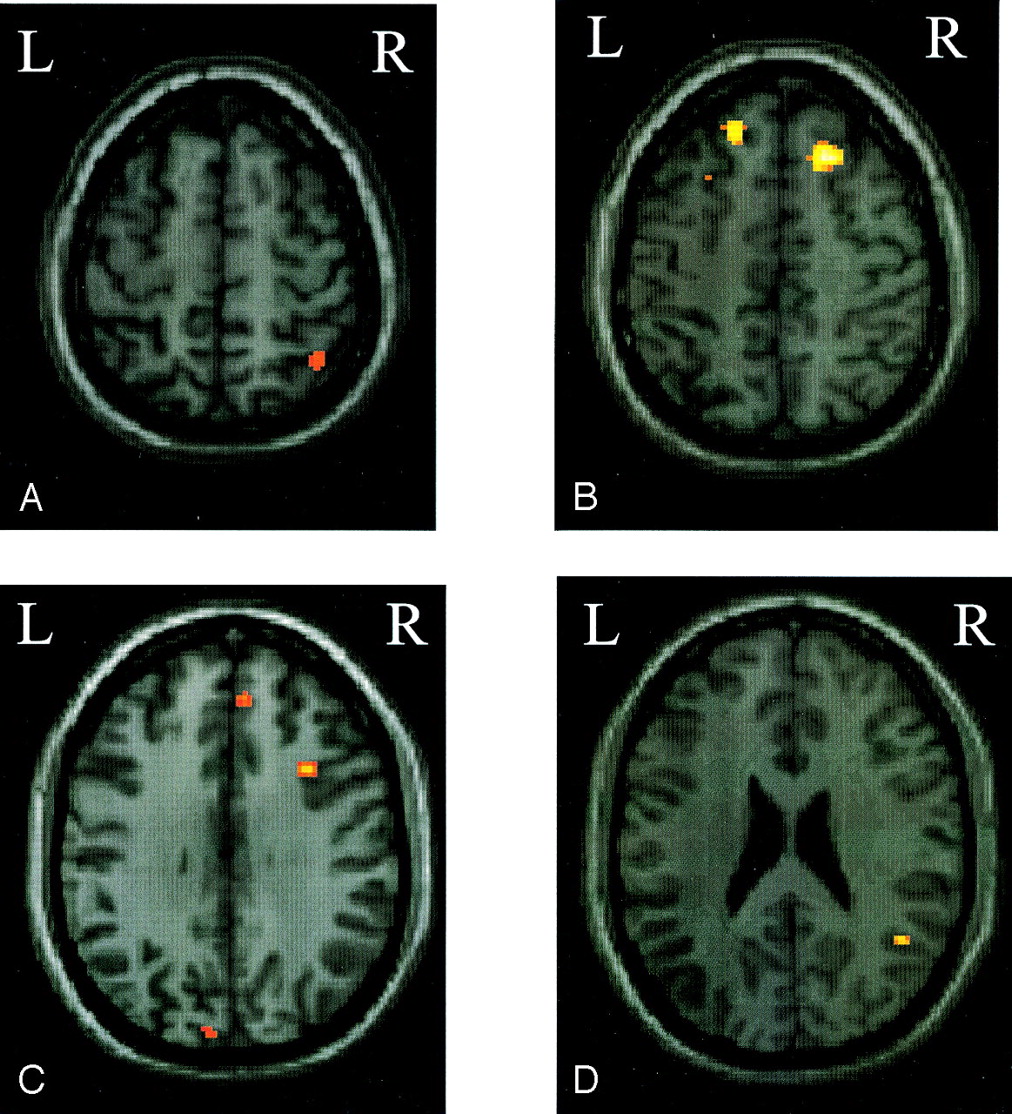

Compared with patients who went on to develop MS, those patients with no evolution had more significant activations of the contralateral primary SMC (SPM space coordinates: −20, −28, 64), contralateral SMA (SPM space coordinates: −4, 0, 60), ipsilateral parietal portion of the paracentral lobule (SPM space coordinates: 6, −46, 64), and ipsilateral cerebellar hemisphere (SPM space coordinates: 18, −58, −22) (Fig 1). On the contrary, compared with those patients without a disease evolution, patients who developed MS had more significant (bilateral) activations of the SFS (SPM space coordinates: 24, 26, 52 and −26, 18, 52), the superior frontal gyrus (SFG) (SPM space coordinates: 6, 50, 46 and −6, 36, 50), the IPS (SPM space coordinates: 40, −56, 60 and −30, −74, 36) (Fig 2), and the putamen (SPM space coordinates: 20, 2, 10 and −18, 2, 14). They also showed more significant activations of the ipsilateral MFG (SPM space coordinates: 34, 16, 34), STG (SPM space coordinates: 46, −54, 24) (Fig 2), and cuneus (SPM space coordinates: 22, −56, 14), as well as of the contralateral fusiform gyrus (SPM space coordinates: −22, −52, −4).

Color-coded SPMt maps superimposed on a high-spatial-resolution T1-weighted image showing relative cortical activations during a simple motor task with the dominant, functionally normal right hand in patients with clinically isolated syndromes suggestive of MS that did not evolve to definite MS compared with those who did (random effect analysis, between-group comparison, corrected P value < .05).

A, Ipsilateral paracentral lobule.

B, Contralateral primary somatomotor cortex and supplementary motor area.

C, Ipsilateral cerebellar hemisphere.